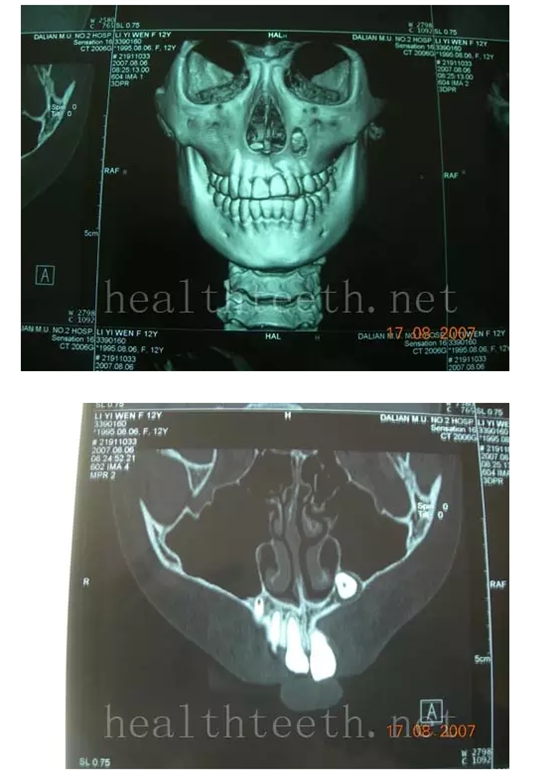

2、埋伏牙

左上乳3滯留,恒3未見萌出,曲面斷層片顯示牙齒埋伏

QQ圖片20150722094029.png

通過CT片確定埋伏牙齒具體的位置,顯示距離左側上頜竇很近,偏唇側,這為手術定位提供了方便

QQ圖片20150722094055.png